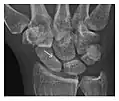

Figure 3: A 26-year-old man presenting with wrist pain after being assaulted. (a) Initial anteroposterior radiograph shows a subtle linear lucency within the scaphoid extending to the scaphocapitate articular surface that was overlooked (arrow). (b) Initial "scaphoid" view was negative. (c) Followup anteroposterior radiographs, 12 days later, shows obvious scaphoid fracture (arrows).[1]

Figure 4: Dorsal triquetral fracture of the left wrist in a 30-year-old man after a trauma. (a) Anteroposterior radiograph shows a normal appearance. (b) Lateral radiograph of the same wrist demonstrates a chip fracture off the dorsal aspect of the triquetrum (arrow).[1]